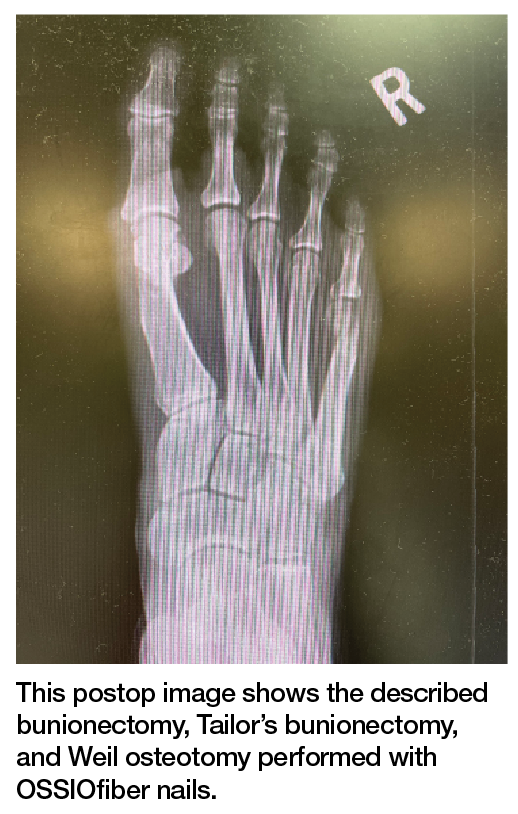

The Bio-Integrative OSSIOfiber Trimmable Fixation Nail (OSSIO) was made to be as rigid as a screw, trimmable to be flush with the bone, and offer a form of compression unlike a screw but just as stable in my hands. What was more the nail needed to require very few steps to place. Place a pin, drill over the pin, and place the nail. The nail could be placed and trimmed flush if only one cortex was drilled or it could be measured like a screw, trimmed, and inserted according to the right length for bicortical fixation options.

So now what? What type of procedure is ideal for this nail? I have come down to 3 types of osteotomies that I prefer to perform with this system. The first and workhorse for me is a long-arm offset V osteotomy. Perform the osteotomy with a longer dorsal arm, which allows two points of fixation and bicortical fixation. The shift of the eminence can also be pushed a bit further lateral due to the long arm’s increased surface area and contact surface. Achieve fixation by placing two K-wires into the osteotomy bicortically from dorsal to plantar. I find that the depth of the pin is not important. Make a single drill hole with a cannulated drill over the first wire. Measure the length of the drill hole, trim the pin to length with a saw, place the pin into the drill hole, and press fit. Repeat the process with the second pin. What I have found is that the barbs on the nail and the hexagonal shape allow for compression during placement and the compression holds. The osteotomy is inherently stable, and the nails allow stability in multiple planes which, in my experience, allows for immediate weight-bearing.

The second type of osteotomy is an L-style osteotomy for decompression, plantarflexion, and cartilage angulation correction needs. This type of osteotomy is again inherently stable but the intermetatarsal angle correction cannot be pushed as far. However, I find it is easier to correct cartilage rotation and plantarflex an elevated metatarsal. Fixation is done through one dorsal-to-plantar and proximal-to-distal pin, much like a screw. I place a second pin from medial-to-lateral and proximal-to-distal to reduce rotation and angulation. The placement is slightly different in that the two pins are placed, drilling is unicortical, not bicortical, and measuring is not necessary. Place the pins until they hit the distal cortex and the cut flush to the bone.